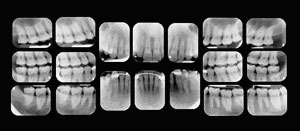

Your first visit to the doctor typically includes an x-ray that allows the doctor to view the structure of the jaw, the position of any teeth that have not yet erupted, malformed roots, and tooth decay.

New patients eighteen years or older will be scheduled with one of our dentists. Your first visit will include any necessary x-rays, an oral cancer exam and a very thorough exam of your mouth and teeth. Your dentist will review proper brushing techniques, review x-rays and discuss treatment options with you. Following your appointment, you will speak with one of our treatment coordinators to review your information, insurance benefits and our financial policy. If treatment is necessary, we will schedule your next appointment.

New patients under the age of 18 will be scheduled with one of our hygienists. She will take any necessary x-rays, clean and polish your teeth, review proper brushing techniques, apply fluoride when appropriate and conclude with an exam from your dentist.